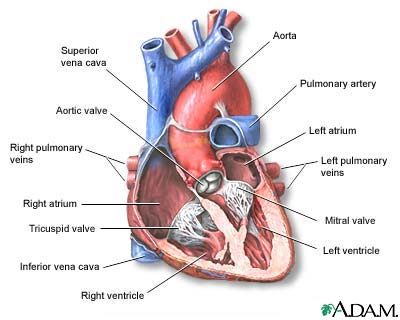

Total anomalous pulmonary venous return (TAPVR) is a heart disease in which the 4 veins that take blood from the lungs to the heart do not attach normally to the left atrium (left upper chamber of the heart). Instead, they attach to another blood vessel or the wrong part of the heart. It is present at birth (congenital heart disease).

In normal circulation, blood is sent from the right ventricle to pick up oxygen in the lungs. It then returns through the pulmonary (lung) veins to the left side of the heart, which sends blood out through the aorta and around the body.

In TAPVR, oxygen-rich blood returns from the lungs to the right atrium or to a vein flowing into the right atrium, instead of the left side of heart. In other words, blood simply circles to and from the lungs and never gets out to the body.

For the infant to live, an atrial septal defect (ASD) or patent foramen ovale (passage between the left and right atria) must exist to allow oxygenated blood to flow to the left side of the heart and the rest of the body.

Surgery to repair the problem is needed as soon as possible. In surgery, the pulmonary veins are connected to the left atrium and the defect between the right and left atrium is closed.